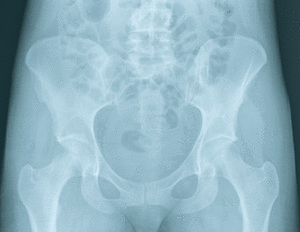

Les 206 os du corps humains peuvent être classés selon deux méthodes fondamentales. La premièrerepose sur la localisation anatomique de l’os, qui est axiale ou appendiculaire. La seconde est basée

sur la forme de l’os, dont on distingue 2 formes principales : les os longs (radius, tibia, fémur…) et

les os plats (crâne, omoplate, côtes…). Ces deux types d’os se distinguent aussi par leur mécanisme

de développement. Les os longs sont formés par ossification endochondrale, c'est-à-dire une

ébauche cartilagineuse qui est remplacée in fine par du tissu osseux. Quant aux os plats, ils sont

formés par ossification membranaire, sans ébauche cartilagineuse préalable. Nous nous

concentrerons dans ce travail essentiellement sur les os longs.